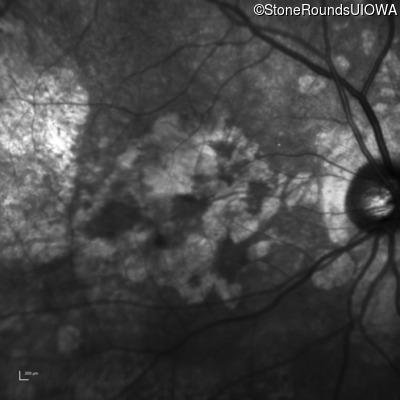

Age at visit: 64 years

OD OS

This 64 year old woman first noticed some distortion in her vision at age 46 while looking at graph paper.